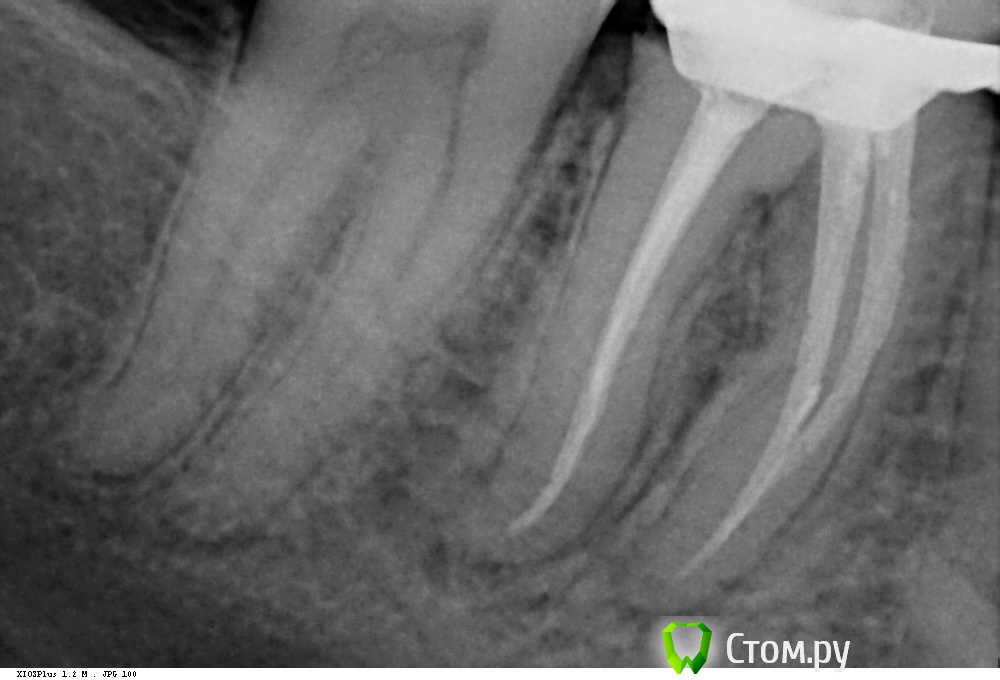

Shaid Опубликовано 28 января, 2014 Поделиться Опубликовано 28 января, 2014 Здравствуйте, уважаемые коллеги! Читаю форум с сентября 2011 года по настоящее время. За это время узнал больше, чем за всю учебу в ВУЗе. До сих пор не решался выложить что-либо на ваш суд. Но надо развиваться дальше и то подтолкнуло меня на создание данной темы, в которой я буду выкладывать удачные и не очень случаи из моей практики.Буду благодарен за любую критику. Итак, неделю назад пришла пациентка с желанием "подлечить все". После ОПТГ было решено начать с 4.6 зуба(кроме того, этот зуб начали лечить месяц назад, положив мышьяк, но не долечили). Глянув на снимок и ужаснувшись от длины корней этого зуба(30 мм по замерам оптг), я начал лечение, в первое посещение - ампутировал(да-да, он был живой несмотря на рентгенологич.картину) пульпу и создал доступ в каналы, сделал билд-ап из Vitremer. Во второе - первично прошел каналы и поставил Метапасту(не хватило времени). В третье, сколол клампом свой билд-ап мех, мед.обр-ка Протейперами до f2 насколько хватило длины инструмента, дальше - ручные. Мыл гипохлоритом, гуттой перемешивал. Обтурация - латералка .02 конусными. 10 Ссылка на комментарий

DmitrySH Опубликовано 28 января, 2014 Поделиться Опубликовано 28 января, 2014 Серьезная длина Молодец, хорошо справился Ссылка на комментарий